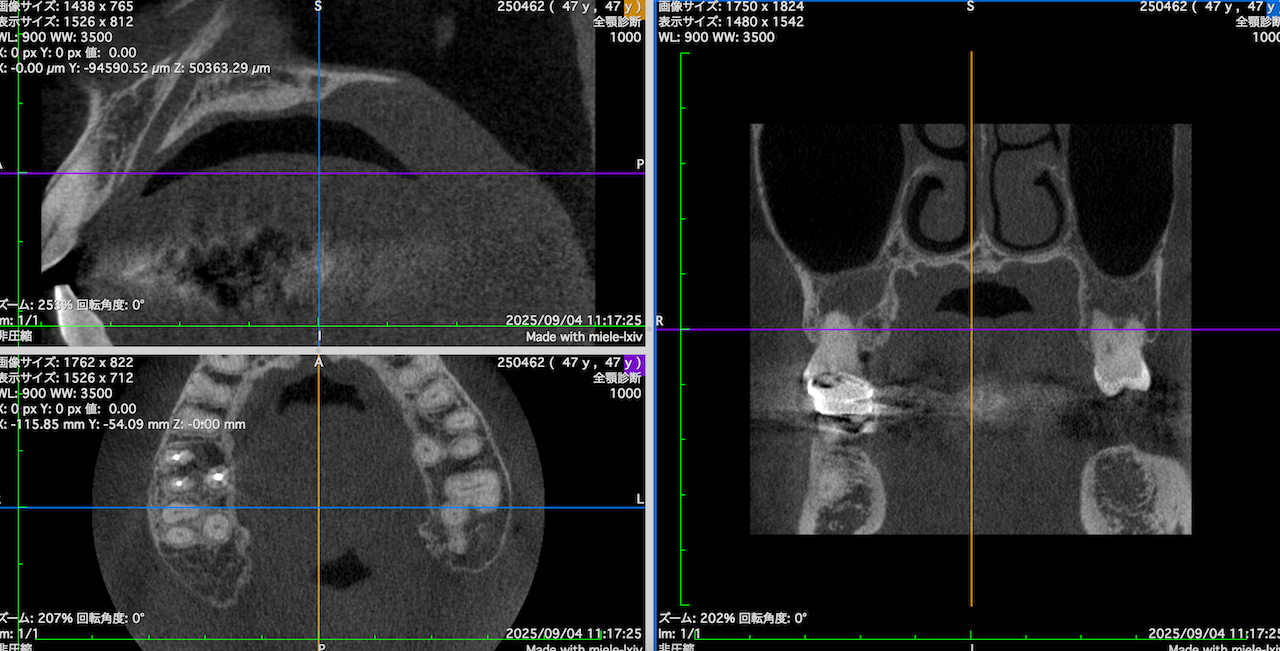

CBCTを立ち上げると以下のような絵になるがこれでは何もわからない。

この絵を以下のような絵にしていく。

#3のMB,DB両方に病変がある。

これを分析しなければならない。